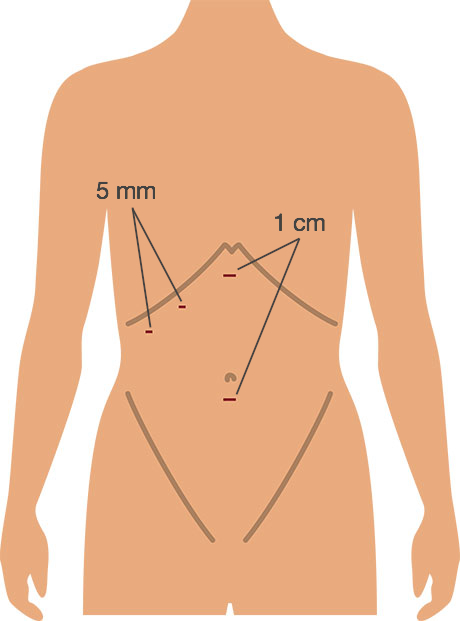

What does a keyhole operation to remove the gall bladder involve?Cholecystectomy is usually carried out by the laparoscopic (‘key hole’) method. Three or four small cuts are made in the abdomen. Each of these cuts is generally no more than 1 cm in length. The abdomen is then blown up with carbon dioxide (CO2) gas. This lifts the abdominal wall upwards, and gives the surgeon space to operate. The gall bladder is removed using a special laparoscopic camera and instruments. The operation usually takes 30 to 90 minutes. At the end of the operation the carbon dioxide gas is let out.